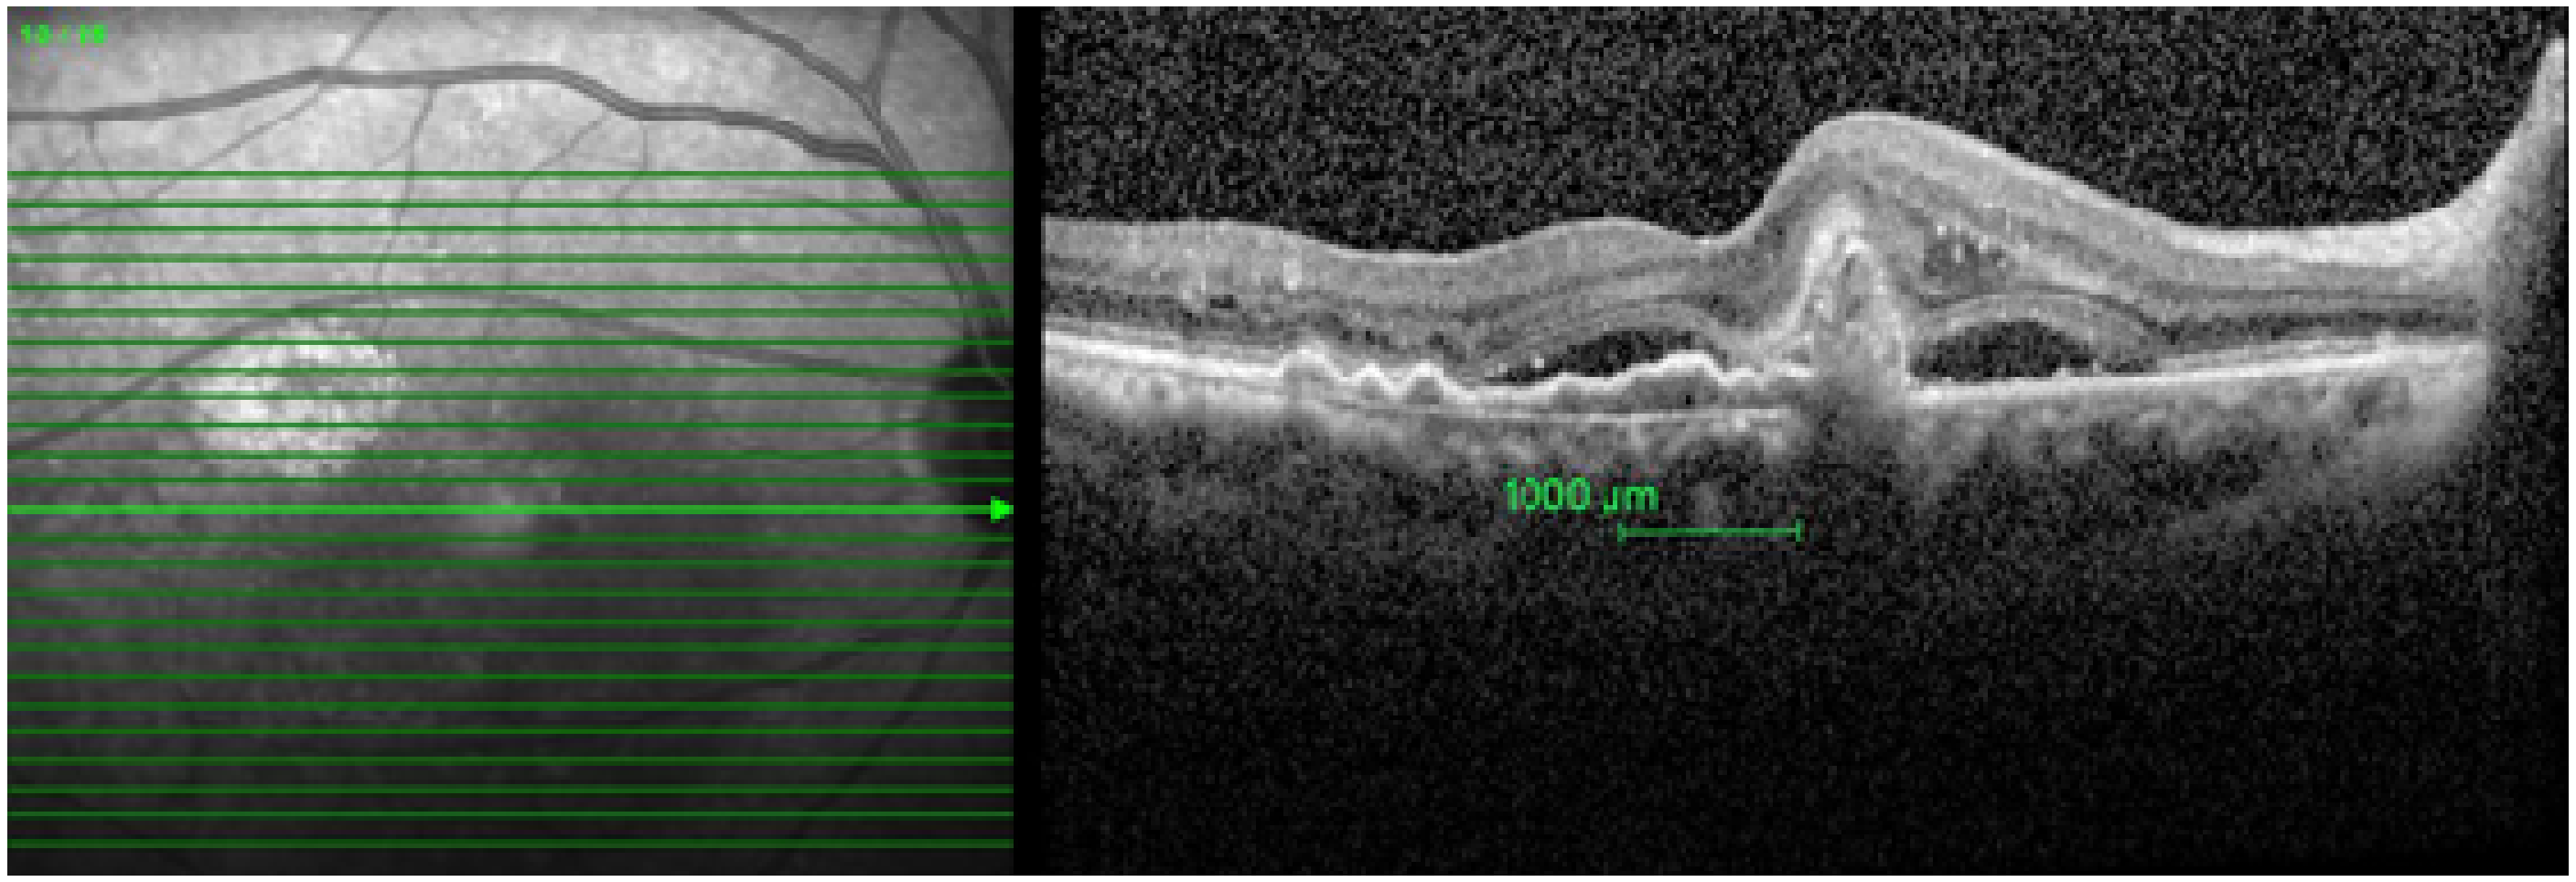

- Integrity of photoreceptors inner segment and outer segment (IS-OS) junction, external limiting membrane (ELM), and retinal pigment epithelium-Bruch’s membrane (RPE-BM) complex were graded as intact or disrupted. When a 75 percent or more part of ELM, IS-OS junction, and RPE-BM complex 1 mm center of the fovea was present, it was graded as intact. When less than 75 percent of ELM, IS-OS junction, and RPE-BM complex was present, it was graded as disrupted.

- Presence of the following pathologies was recorded 1000 microns (1 mm) within the fovea:

- Retinal pigment epithelium detachment (PED)—It is the separation of retinal pigment epithelium (RPE) from the RPE-BM complex.

- Sub-retinal fluid (SRF)—It is seen from the outer border of the RPE to the outer segment of the photoreceptor.

- Polyp—It is the hypo reflective lumen attached to the posterior surface of PED.